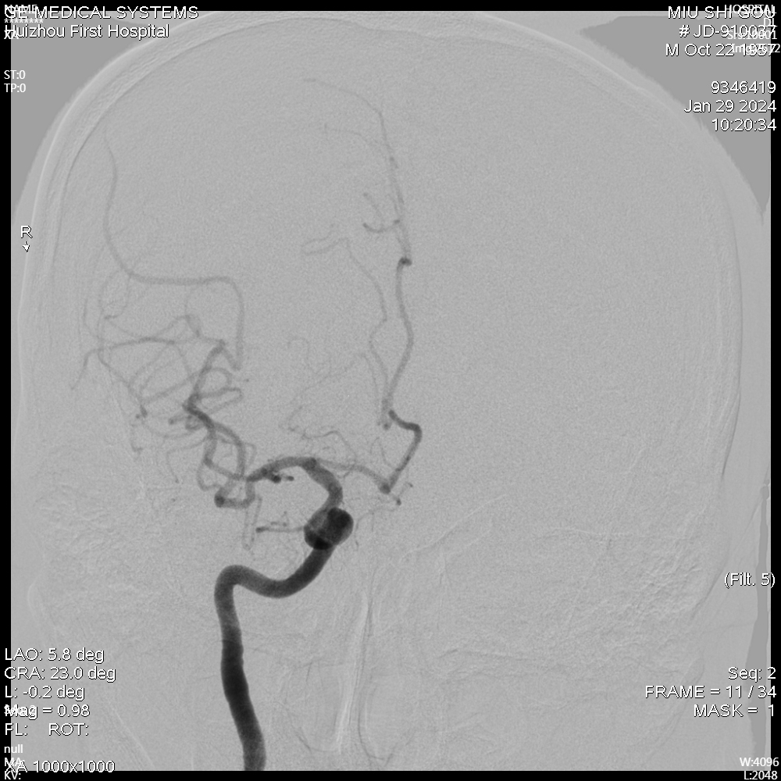

急诊DSA未见畸形血管。

术前诊断:1.脑出血2.高血压3.右侧大脑中动脉中度狭窄。

急诊DSA(右侧颈内正位)

右侧颈外侧位

右侧椎动脉正位片

右侧椎动脉侧位片